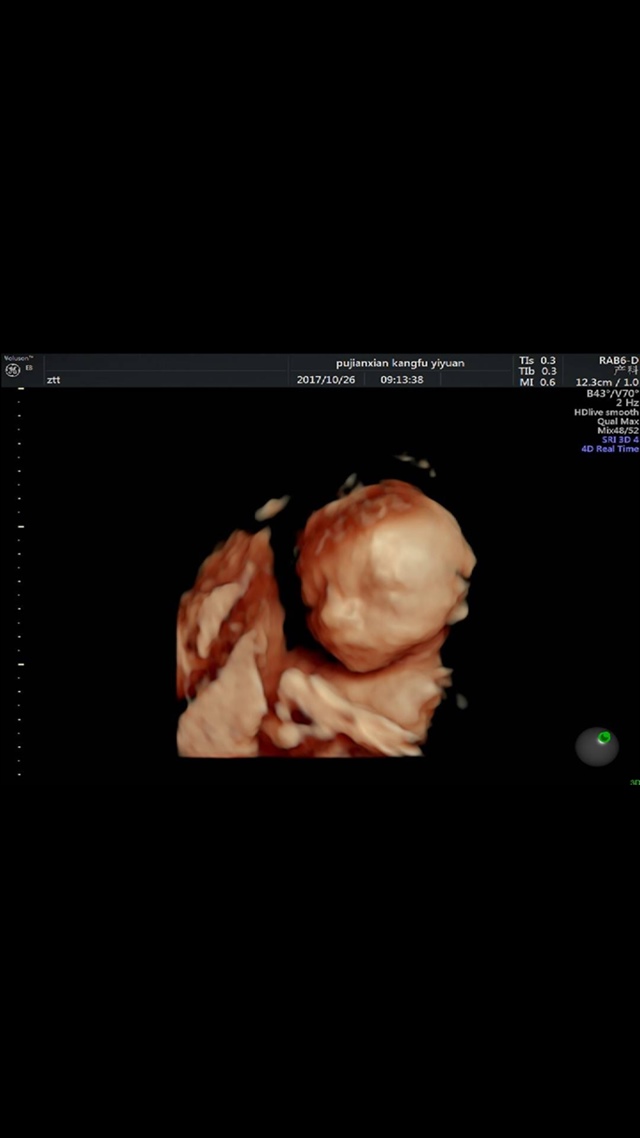

宝宝7个月3天

打隔

孕8周+4天

打嗝